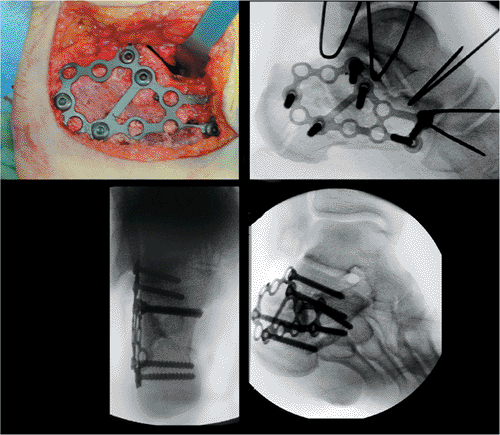

![]() |

Figure 35.30. Definitive fixation of articular surface. A. Lag screw (3.5 mm) is placed with antirotation K wires in place. B. X-ray verifies anatomic joint reduction. Gap is closed and the articular surface is aligned perfectly (white arrow).

lateral fluoroscopic view, cancellous fully threaded 4.0-mm screws are

is verified fluoroscopically, and all K wires are removed (Fig. 35.32).

Figure 35.32. Plate in position with final x-rays showing anatomic reduction of the fracture.